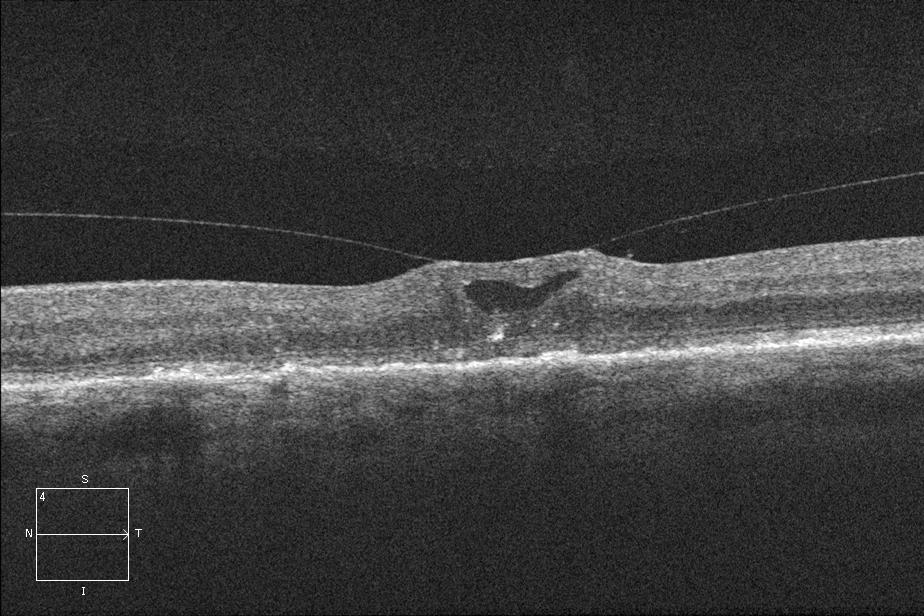

Many authors have identified a subset of VMT called vitreofoveal traction (VFT) where the vitreomacular attachment is limited to a focal foveal region (as shown in the figure above) differentiating it from classic VMT. Prior classifications of VMT are summarized in the section on OCT presented above.

Optical coherence tomography (OCT) allows noninvasive visualization and imaging of vitreomacular interface and is an important tool in the diagnosis and management of VMT syndrome, especially with the advent of non-surgical management with pharmacologic vitreolysis. The OCT in VMT demonstrates a partial posterior vitreous detachment with persistent vitreous attachment to the fovea alone or in addition to the macula and/or the optic disc margin. The posterior hyaloid usually appears as a hyperreflective and thickened line/band on OCT located posterior to the hyporeflective vitreous and anterior to the retina. The appearance of VMT is accentuated when the sensitivity if the image is increased (by making the image lighter in the OCT machine). It courses in a conical pattern posteriorly to attach to the macula.[11][17] According to Chang et al., the hyperreflective band corresponds to the bridging fibrocellular proliferative tissue.[17]

The International Vitreomacular Traction Study Group definitions and classifications mentioned above are a recent attempt to standardize terminologies. However, the present knowledge about the OCT features of VMT has evolved over time. Yamada and Kishi[25] studied the tomographic features and described two types of vitreous traction profiles in VMT:

- (i) V shaped - the vitreous cortex is detached from the retina both temporal and nasal to the fovea, and attached only to the fovea, and

- (ii) J shaped[11] or arc shaped - the vitreous cortex is detached from the retina temporal to the fovea, but remains attached to the retina nasal to the fovea and to the fovea itself.

Other studies have differentiated similarly, between a narrow focal foveolar adhesion (vitreofoveolar traction, a subtype of VMT) causing tractional cystoid macular edema versus a broad macular adhesion (classic VMT) which often has a dumbbell shaped configuration and spans several disc diameters in size, with both types being equally prevalent.[9]

Johnson has graded VMT with a vitreofoveal adhesion

- ≤500 μm as vitreofoveolar traction syndrome and

- that around 1500 μm as classic VMT syndrome.[9]